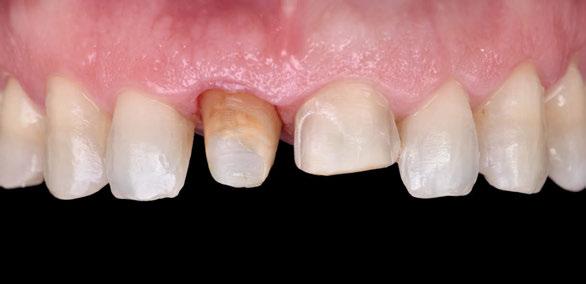

Figura 1. Caso clínico 1. Situación clínica basal de una paciente que presenta recesiones gingivales con pérdida de inserción interproximal en el quinto sextante. A la exploración se observa una profundidad de sondaje incompatible con salud en centro-vestibular del diente en posición de 41, presumiblemente combinado con una dehiscencia ósea.

Paciente de 32 años de edad que acude a la consulta preocupada por la situación de su diente en posición de 41. Le preocupa tanto a nivel de salud como a nivel estético. Además, refiere incapacidad para llevar a cabo un correcto cepillado de esa zona e hipersensibilidad dental.

A la exploración clínica presenta una recesión RT3 (23) en el diente en posición de 41. Además, carece de una banda de encía queratinizada adecuada (≥2mm) y presenta una reducción significativa de la